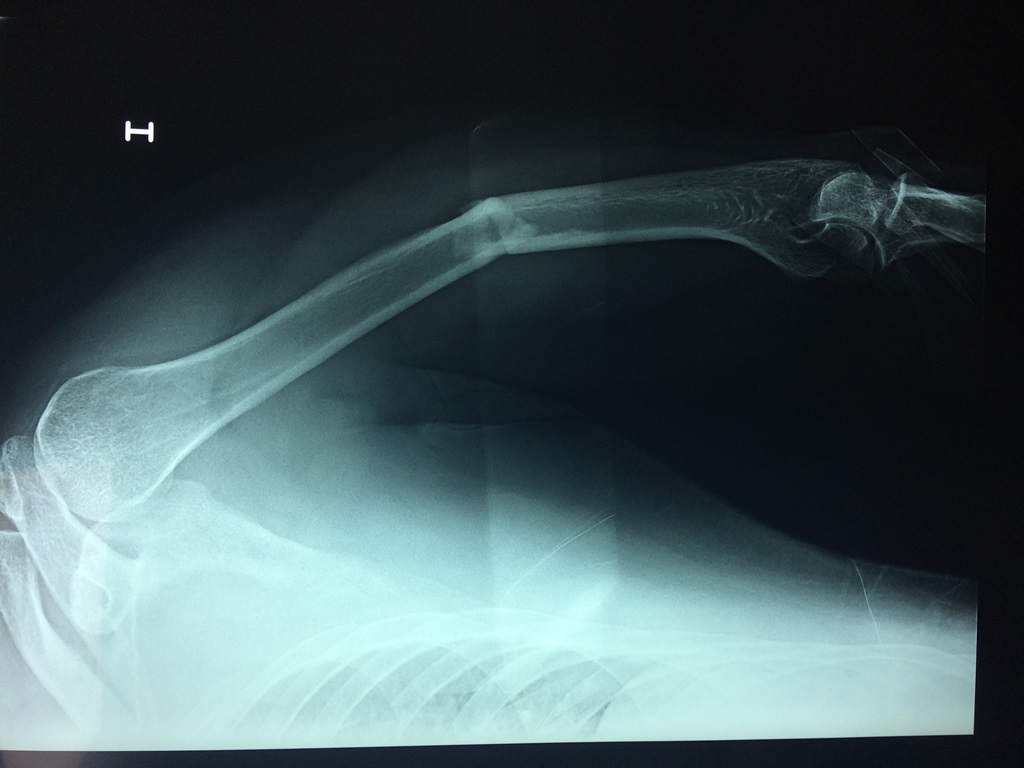

Calcaneo - Húmero

El Húmero (en latín, humerus) es el hueso más largo de las extremidades superiores en el ser humano. Forma parte del esqueleto apendicular superior y está ubicado en la región del brazo. ... El extremo proximal del húmero tiene la cabeza, cuellos quirúrgico y anatómico y tubérculos mayor y menor.